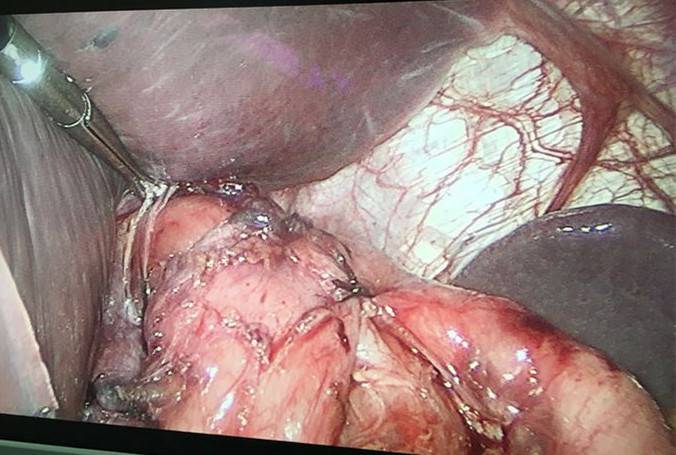

1.胃食管反流病 1.1反流性食管炎LA-B 2.食管裂孔疝 处理:患者诊断明确,行腹腔镜下食管裂孔疝修补术+胃底折叠术。

患者术后一周出院,反酸、烧心、嗳气症状明显缓解,无吞咽不畅等症状。 讨论:对于诊断有食管裂孔疝病人的胃食管反流病,且用药有一定疗效,建议行手术治疗,行腹腔镜下食管裂孔疝修补术,修补了膈裂孔,同时行胃底折叠术,加紧了贲门括约肌压力,共同形成抗“反流瓣”。